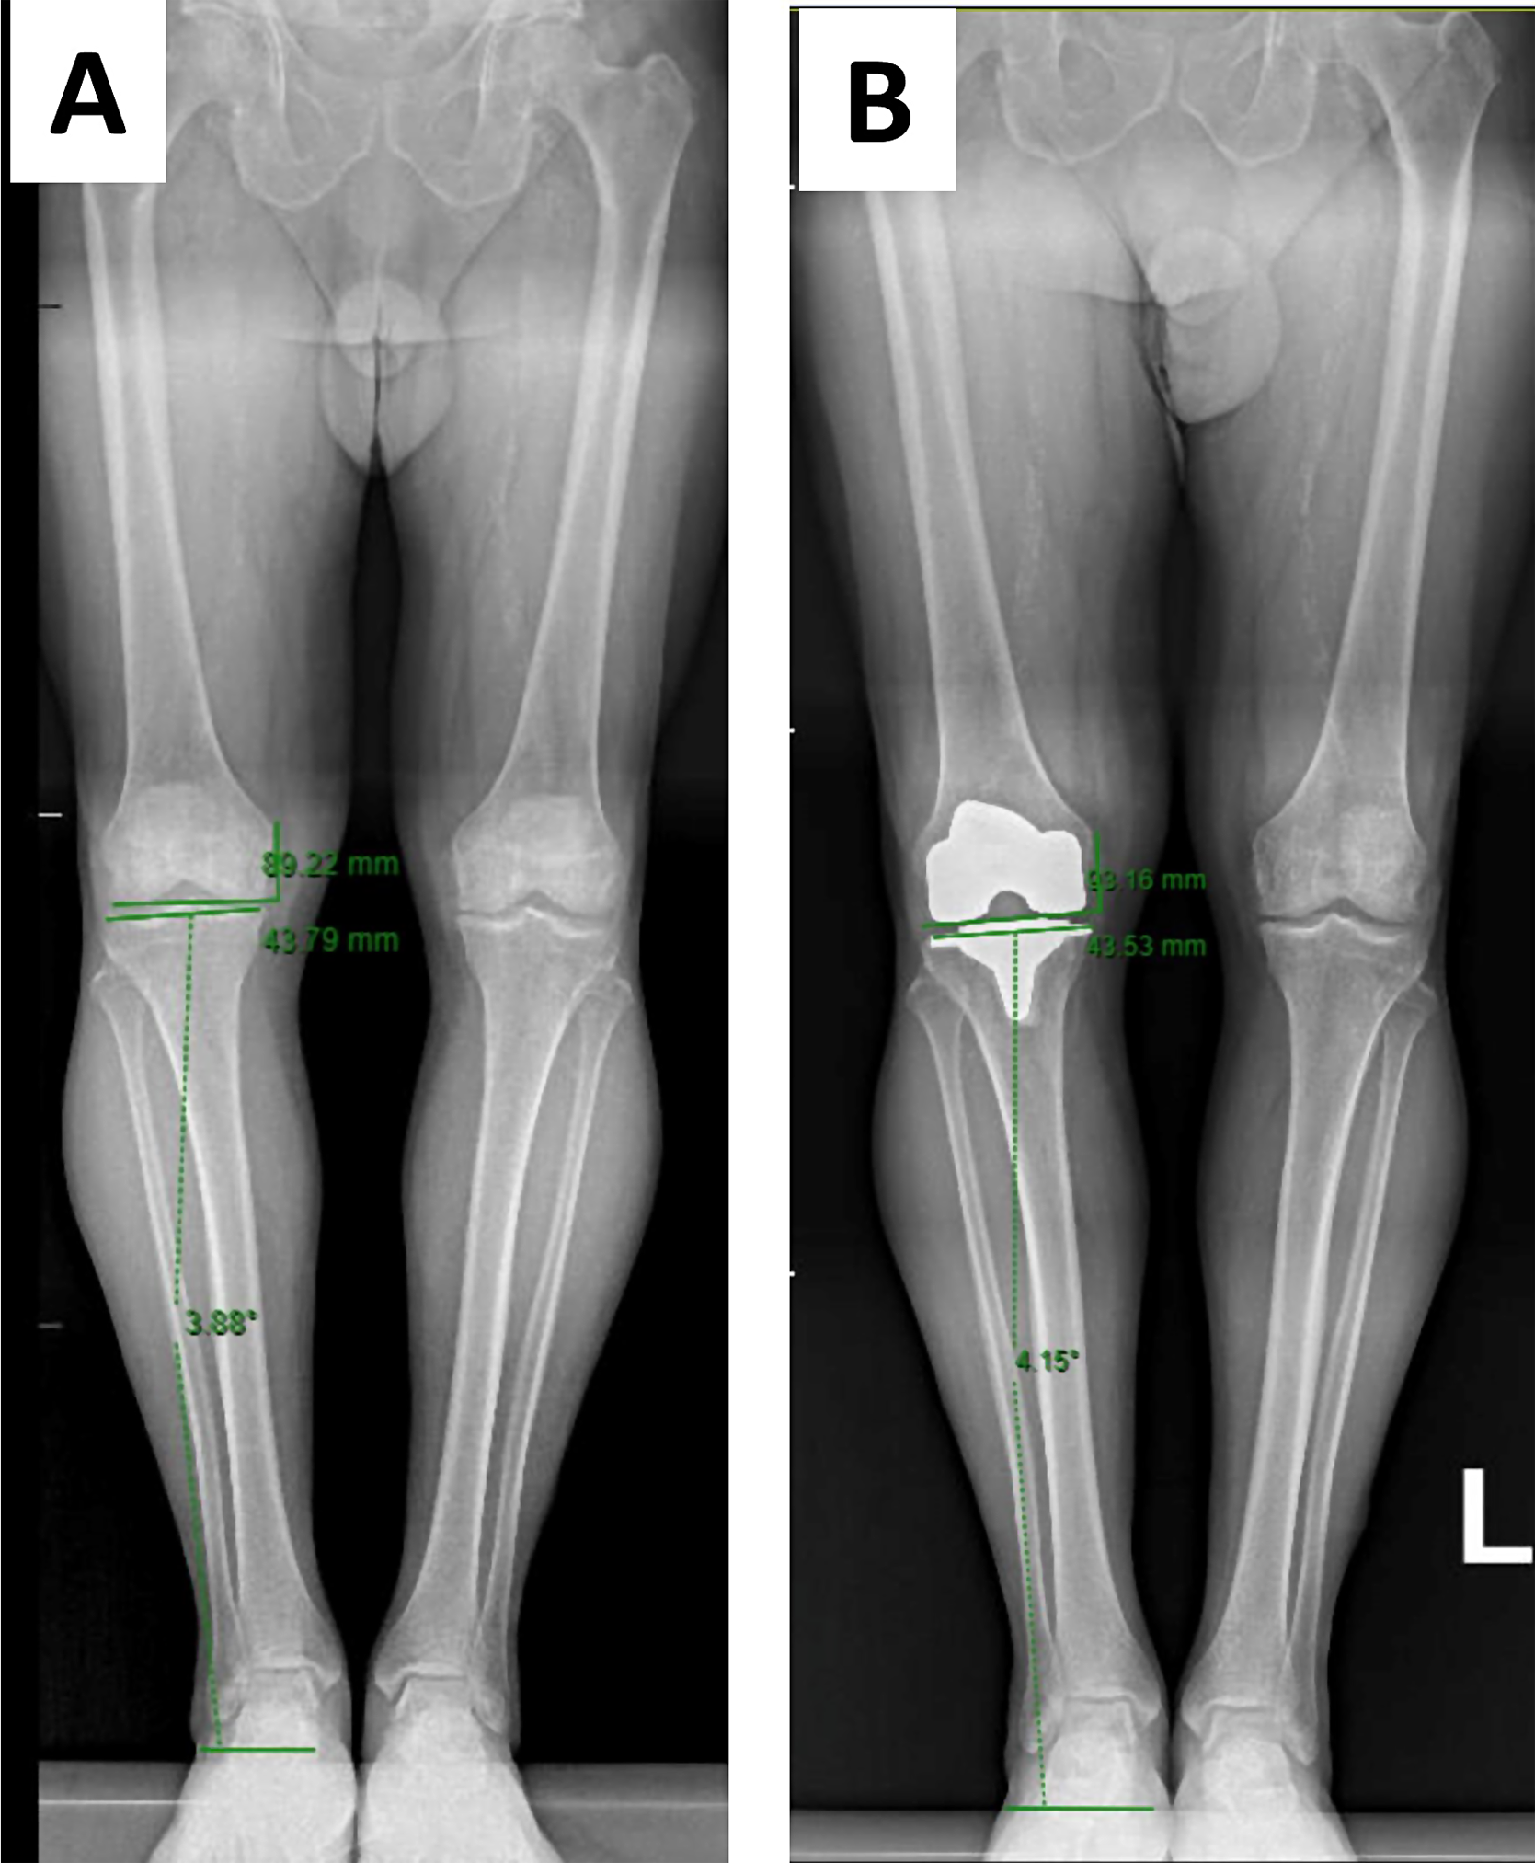

Pre-operative radiographic assessment

Fig. 1

Preoperative (A) and postoperative (B) full-length standing AP radiographs with joint line obliquity and joint line height restoration measurements